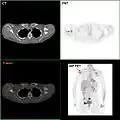

F-18 FDG PET/CT: A breast cancer metastasis to the right scapula